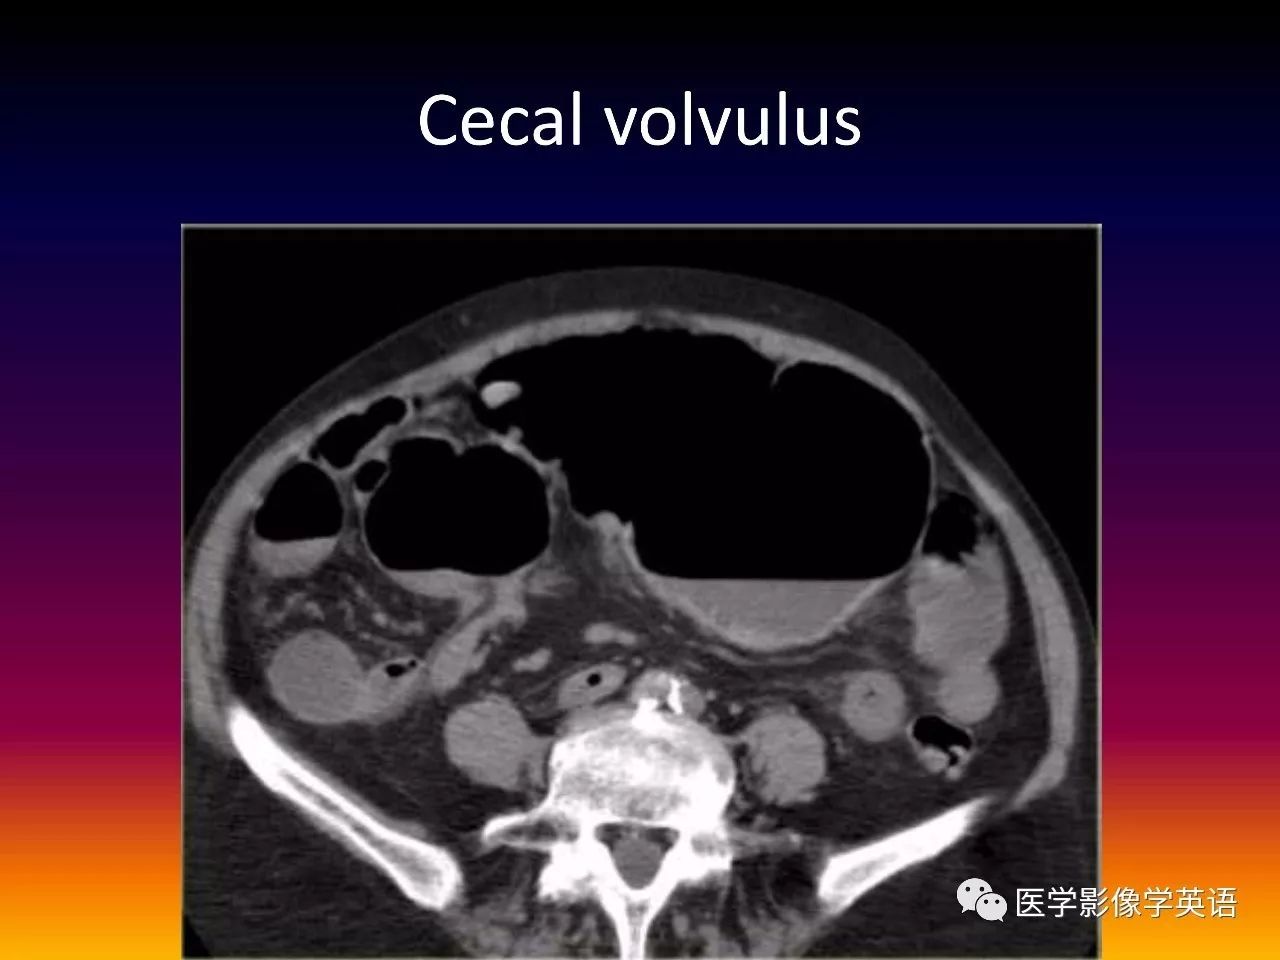

93. Cecal volvulus

94. Cecal volvulus

95. Cecal volvulus

96. Cecal volvulus

97. Cecal volvulus

98. Cecal volvulus

99. Cecal volvulus

100. Cecal volvulus